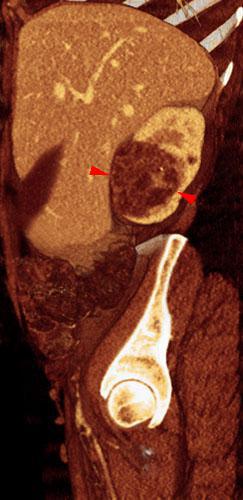

Nefroma quístico multilocular

VR seccional. Visión sagital izquierda. TC contrastado en fase venosa que muestra lesión quística encapsulada y multiloculada (puntas de flecha) que se extiende hacia el hilio renal